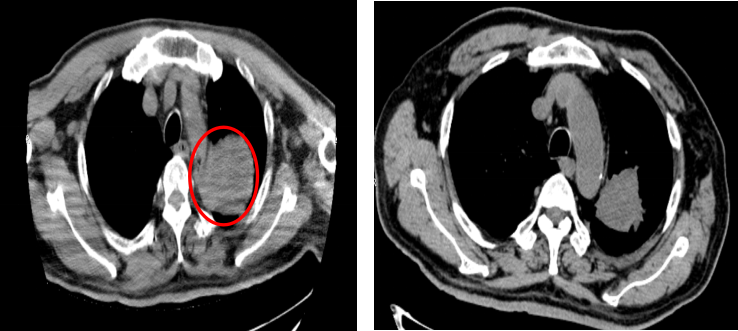

胸部CT(2023年1月):左肺上叶占位并周围阻塞性肺炎,肿块较前缩小,内新发小空洞,周围炎症较前吸收减少。疗效评价为PR。

2.png

胸部CT(左:基线;右:2023年1月)

胸部CT(2023年4月):左肺上叶占位并周围阻塞性肺炎,肿块较前稍缩小。疗效评价维持PR。

3.png

胸部CT(左:基线;右:2023年4月)

胸部CT(2023年10月):左肺上叶占位较前增大,疗效评价为疾病进展(PD)。此时,患者已获得约12个月的无进展生存期。

4.png

胸部CT(左:2023年4月;右:2023年10月)

针对胸部病灶的进展,患者于2023年11月10日开始接受胸部姑息性放疗,放疗总剂量为:PTV 5500cGy,共25次,每次220cGy,放疗期间患者暂停用舒格利单抗。放疗结束后,于2024年1月29日继续重启舒格利单抗维持治疗。截至目前,患者已接受共计31个周期的舒格利单抗维持治疗,并仍在持续治疗中。

后续多次复查,胸部CT均提示病情维持稳定。

图片9.png

胸部CT(2023年11月-2025年3月)